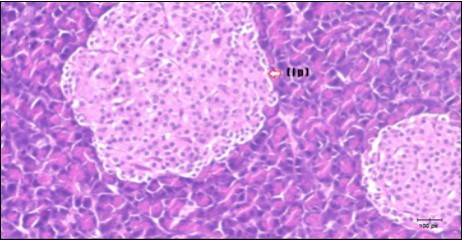

Pancreas Histopathological Observations

Histological examination of pancreas of the control rats showed normal sized islets of pancreas (Ip) compared to the diabetic rats which showed markedly atrophic islets of pancreas (I.p.) (Figure 8 and Figure 9). Pancreas of in groups (3) and (4) rats showed mild atrophic islets of pancreas (I.p.) with inflammatory cellular infiltrate (Figure 10 and Figure 11). The pancreas of rats in group (5) showed nearly normal islets of pancreas (I.p.) with few inflammatory cellular infiltrate (I.c.) (Figure 12).

Figure 9.Photomicrogragh of pancreas section of diabetic rat showing the markedly atrophic islets of Langerhans. (arrow) (H&E) (40X).

Figure 10.Photomicrogragh of pancreas section of treated rat with Fenugreek showing less improved islets of Langerhans with more cells (star). (H&E) (40X).

Figure 11.Photomicrogragh of pancreas section of treated rat with Glimepiride showing mildly improved of isled of Langerhans with large number of cells (dashed-arrow). (H&E) (40X).

Figure 12.Photomicrogragh of pancreas section of treated rat with both Fenugreek and Glimepiride showing nearly normal islets of Langerhans with spindle (arrow) & polygonal cells (dashed- arrow). (H&E) (40x).

Histopathological observation in diabetic control showed degenerative changes in both endocrine and exocrine pancreases. A probable explanation may be related to oxidative stress resulting from hyperglycemia which decreases the antioxidants levels and increases ROS 33 and the activities of antioxidant enzyme were altered in diabetic rats. These effects further exacerbate the development and progression of diabetes complications and these may represent the causes of degeneration revealed in histological sections. Fenugreek improved blood glucose levels and insulin, lowered pancreatic islet and β-cells damage which may be attributed to its immune modulatory activity and insulin stimulation action along with its antioxidant potential 32. Glimepiride caused restoration of morphology of beta cell of diabetic and it increased percentage of beta cells 34. This protective effect could be attributed to the antioxidant properties of Glimepiride. Combination therapy improves the protective effect of both therapies alone.